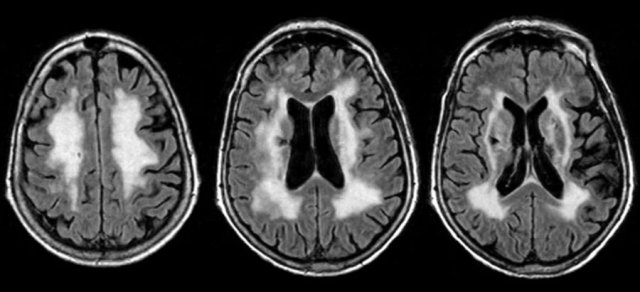

Dissemination in time

For dissemination in time (DIT) there are two possibilities:

- A new T2 and/or gadolinium-enhancing lesion(s) on follow-up MRI, with reference to a baseline scan, irrespective of the timing of the baseline MRI OR

- Simultaneous presence of asymptomatic gadolinium-enhancing and non-enhancing lesions at any time.

On the far left a new T2 hyperintense lesion on a follow-up examination 3 months after the first clinical event.

The images on the right show a new enhancing lesion on a follow up scan.